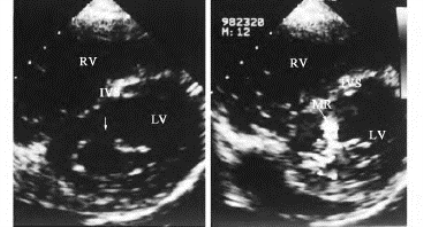

1.24.2二、肥厚型心肌病